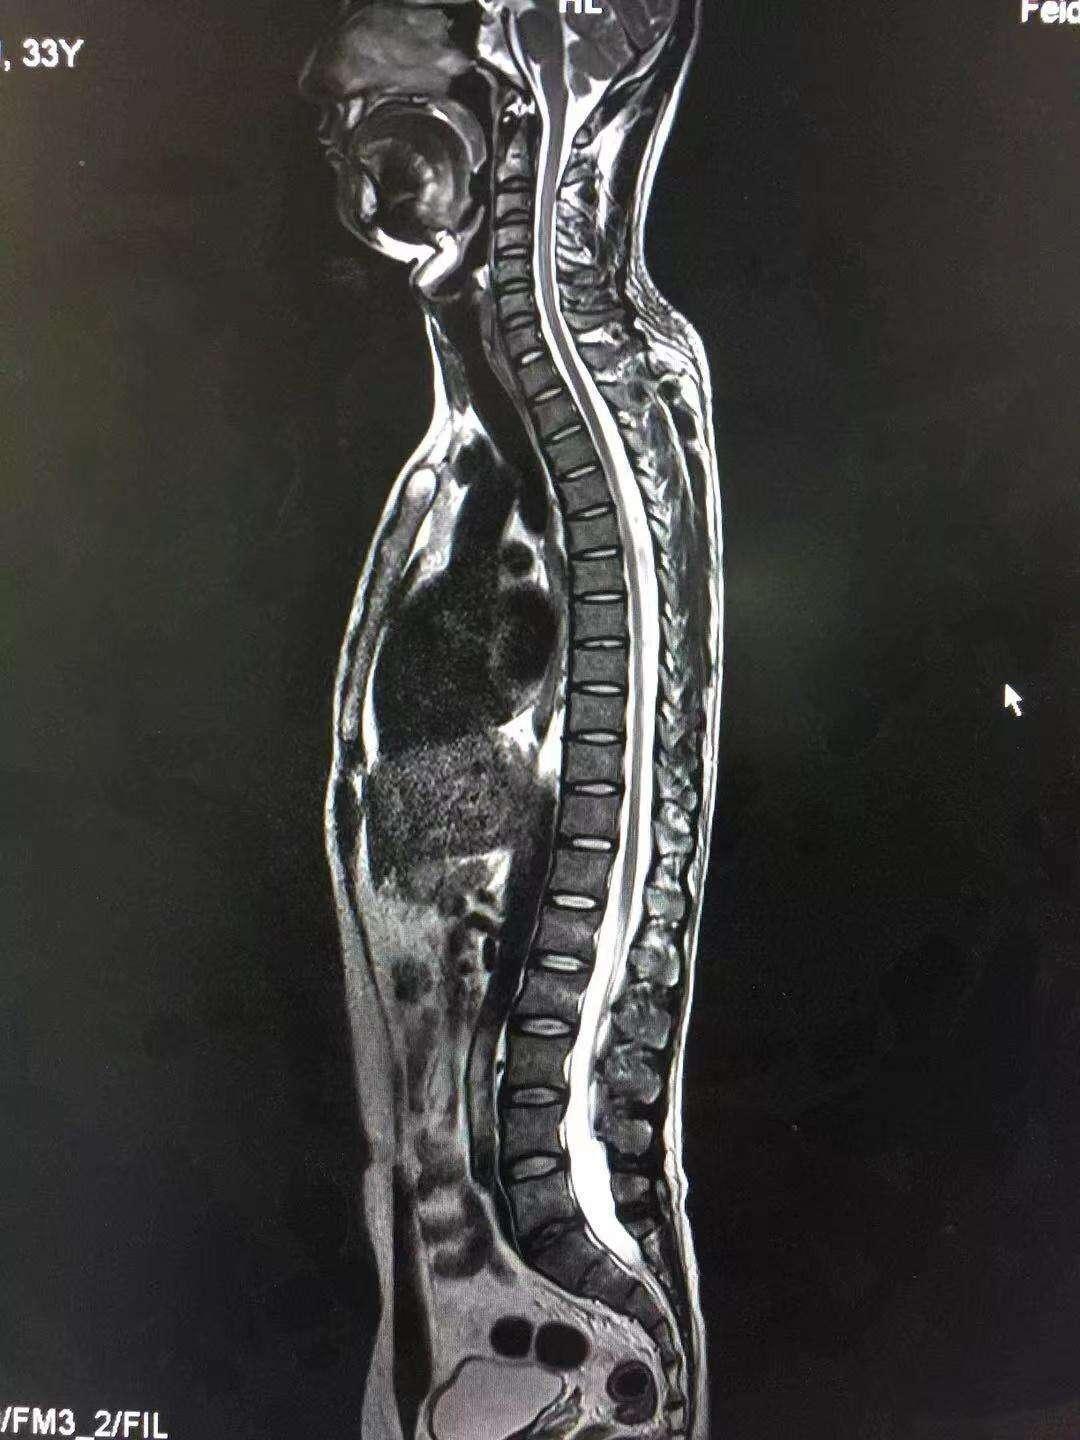

圖片來源:作者提供

MRI它利用的是人體內含量最多的氫質子也就是水來進行成像。MRI的成像原理就像我們把一瓶礦泉水用力搖晃,之後觀察水旋轉,水共振的情況,利用特殊的設備採集信號,再通過計算機處理得到圖像信息。

它的優勢很多,顱腦、脊髓、骨與關節軟骨、滑膜、韌帶等部位的病變首選MRI檢查。

神經系統病變、心血管系統及胸部病變、腹部器官、盆腔臟器,直腸、前列腺和膀胱的腫物等、全身軟組織病變,無論來源於神經、血管、淋巴管、肌肉、結締組織的腫瘤、感染、變性病變等,MRI檢查皆可做出較爲準確的定位、定性的診斷。

人體內組織含水量達百分之七十,故而,它對人體的軟組織顯示效果較CT更清楚。除了肺部掃描(這是CT的王牌),其它只要你能想到的部位,基本上都是可以做的。但是,MRI就可以因此百無禁忌嗎?